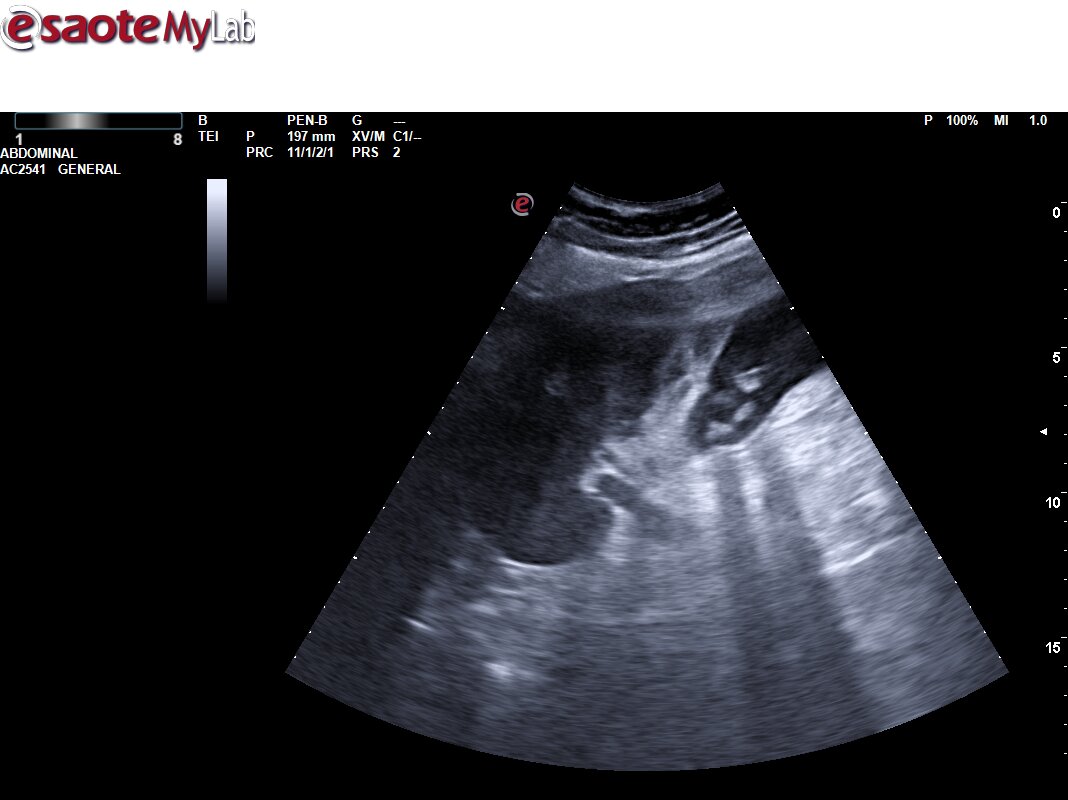

Ecografía primaria. Se aprecia vesícula con aumento de la pared de la vesícula biliar de unos 10 mm, con signos flogóticos (aumento de captación Doppler y líquido libre perivesicular), con contenido hiperecogénico en su interior con sombra posterior, y dilatación de vía intrahepática. Vía extrahepática no valorable por interposición de gases. Colecistitis. Dilatación de vía intrahepática.